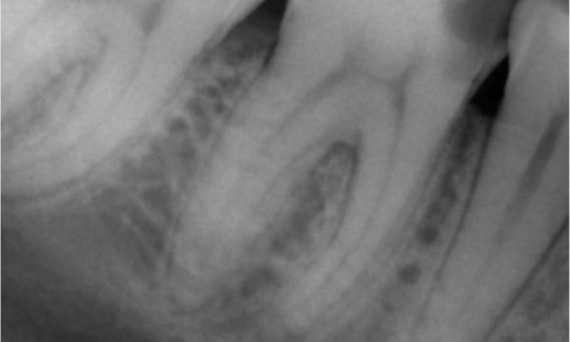

Antes: No exame, havia uma lesão de cárie dental relacionada ao primeiro molar inferior direito. O exame radiográfico revelou proximidade da lesão ao corno pulpar e, combinando-a com a queixa principal, concluiu-se um diagnóstico final de pulpite crónica irreversível.

Depois: A cavidade de acesso foi realizada da maneira mais conservadora possível. TruNatomy foi o sistema de escolha devido à idade do paciente jovem. Precisávamos preservar a dentina o máximo possível para aumentar a capacidade do dente de superar a carga oclusal e aumentar a longevidade da restauração final.

Dr. Ahmed Hussein Abuelezz (PhD em Endodontia)

Cairo, Egito